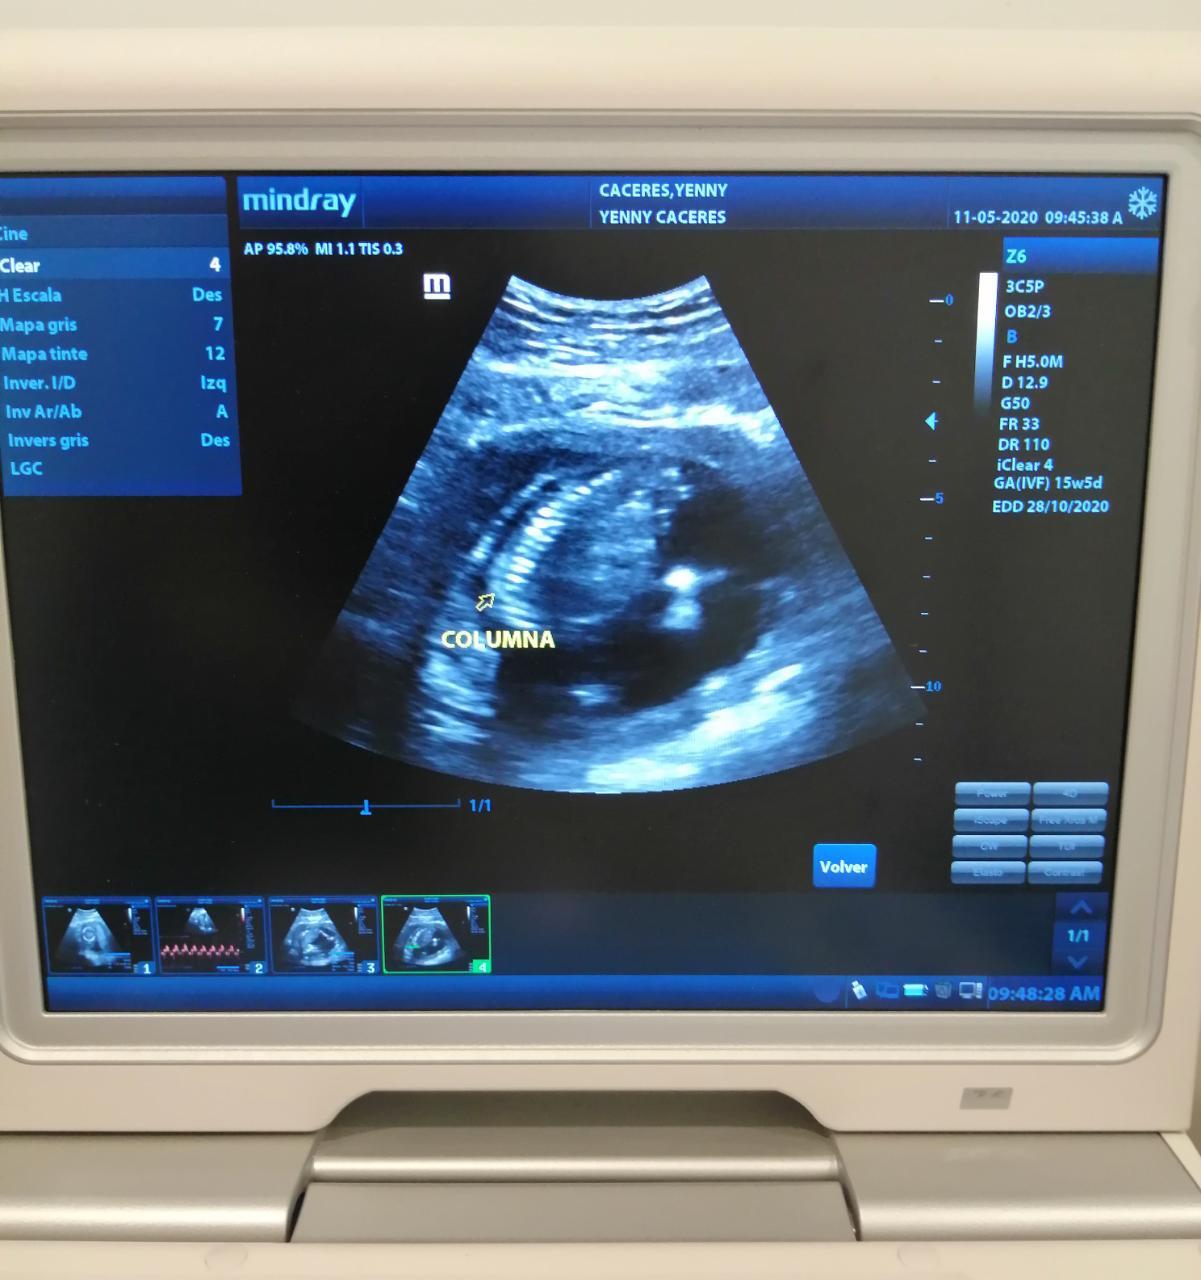

ULTRASON